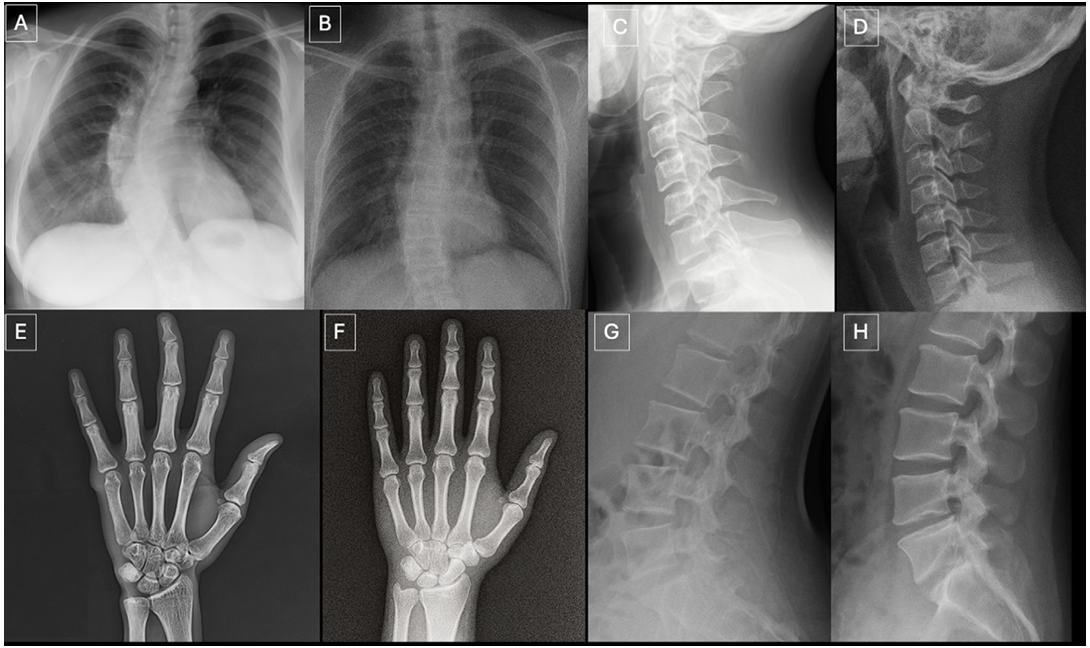

첫 번째 실험은 흉부, 척추, 손과 같은 다양한 부위의 X선 이미지 154장을 무작위로 보여주면서 이미지의 품질과 진단 가능성을 평가하도록 하였다. 이 중 절반은 ChatGPT-4o가 생성한 가짜 이미지이고 나머지 절반은 실제 환자의 영상이었다. 첫 번째 실험에서는 참가자들에게 연구의 목적을 알리지 않은 채 각 이미지의 화질을 평가하고 진단을 기록하게 하였으며, 마지막에 자유롭게 이 이미지에서 이상한 점이 있었는지 묻는 질문을 남겨두었다.

두 번째 실험에서는 참가자들에게 데이터 세트에 합성 이미지가 포함되어 있음을 알리고 각 이미지가 진짜인지, 인공지능으로 생성된 것인지를 분류하도록 하였다. 그 결과 방사선 전문의들이 진짜와 가짜를 구분하는 평균 정확도는 74.8%로, 특이도(진짜를 진짜로 맞히는 비율) 80.4%, 민감도(가짜를 가짜로 맞히는 비율) 69.1%를 기록했다. 참가자 17명의 구분 정확도는 최저 58%에서 최고 92%까지 넓게 분포하였으며 경력 연수(8년 이상 vs 8년 미만)와 정확도 사이에는 상관관계가 없었다.

연구진은 여기서 한 걸음 더 나아가, 인공지능에서도 동일한 테스트를 해보았다. GPT-4o, GPT-5, 구글의 Gemini 2.5 Pro, 메타의 Llama 4 Maverick 등 최신 대형 언어 모델에게도 동일한 데이터 세트를 보여주고 해당 이미지들이 진짜인지 가짜인지 구별하도록 한 것이다. 그 결과 GPT-4o는 85.1%, GPT-5는 82.5%의 정확도를 보여 방사선 전문의보다 약간 높은 성능을 보였지만, 그럼에도 불구하고 모든 이미지를 정확히 구별하지는 못했다. Gemini와 Llama는 각각 56.5%, 59.1%의 정확도를 보여 사실상 무작위 수준에 가까운 결과를 보였다. 인공지능이 만든 가짜 이미지를 인공지능조차 완벽하게 구별하지 못하는 상황이 펼쳐진 것이다.